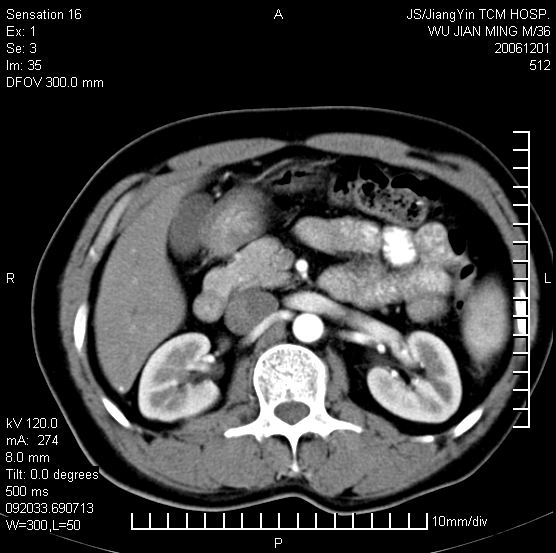

以下是引用dyqct在2006-12-1 21:17:00的发言:[br]左心缘旁及后肋膈窦区见巨大椭圆形混杂密度肿块,周围见大小不等斑片状钙化,内部无强化,周围包膜轻度强化,心脏明显受压变形,即明显占位效应,肿块广基与心包、膈相连。肝、脾内、肝门见多数小结节状钙化影。[br]考虑:1、左心缘旁及后肋膈窦区慢性包裹性胸膜炎(结核性);[br] 2、肝、脾及肝门淋巴结核已钙化。[br]

以下是引用zrs在2006-12-2 17:28:00的发言:[br]肺内、肝脾内虽有钙化,但不支持结核性胸胸膜炎包裹,而支持寄生虫感染![br][br]

以下是引用zyx168在2006-12-2 10:10:00的发言:[br][br]肝脾肺内多发钙化灶